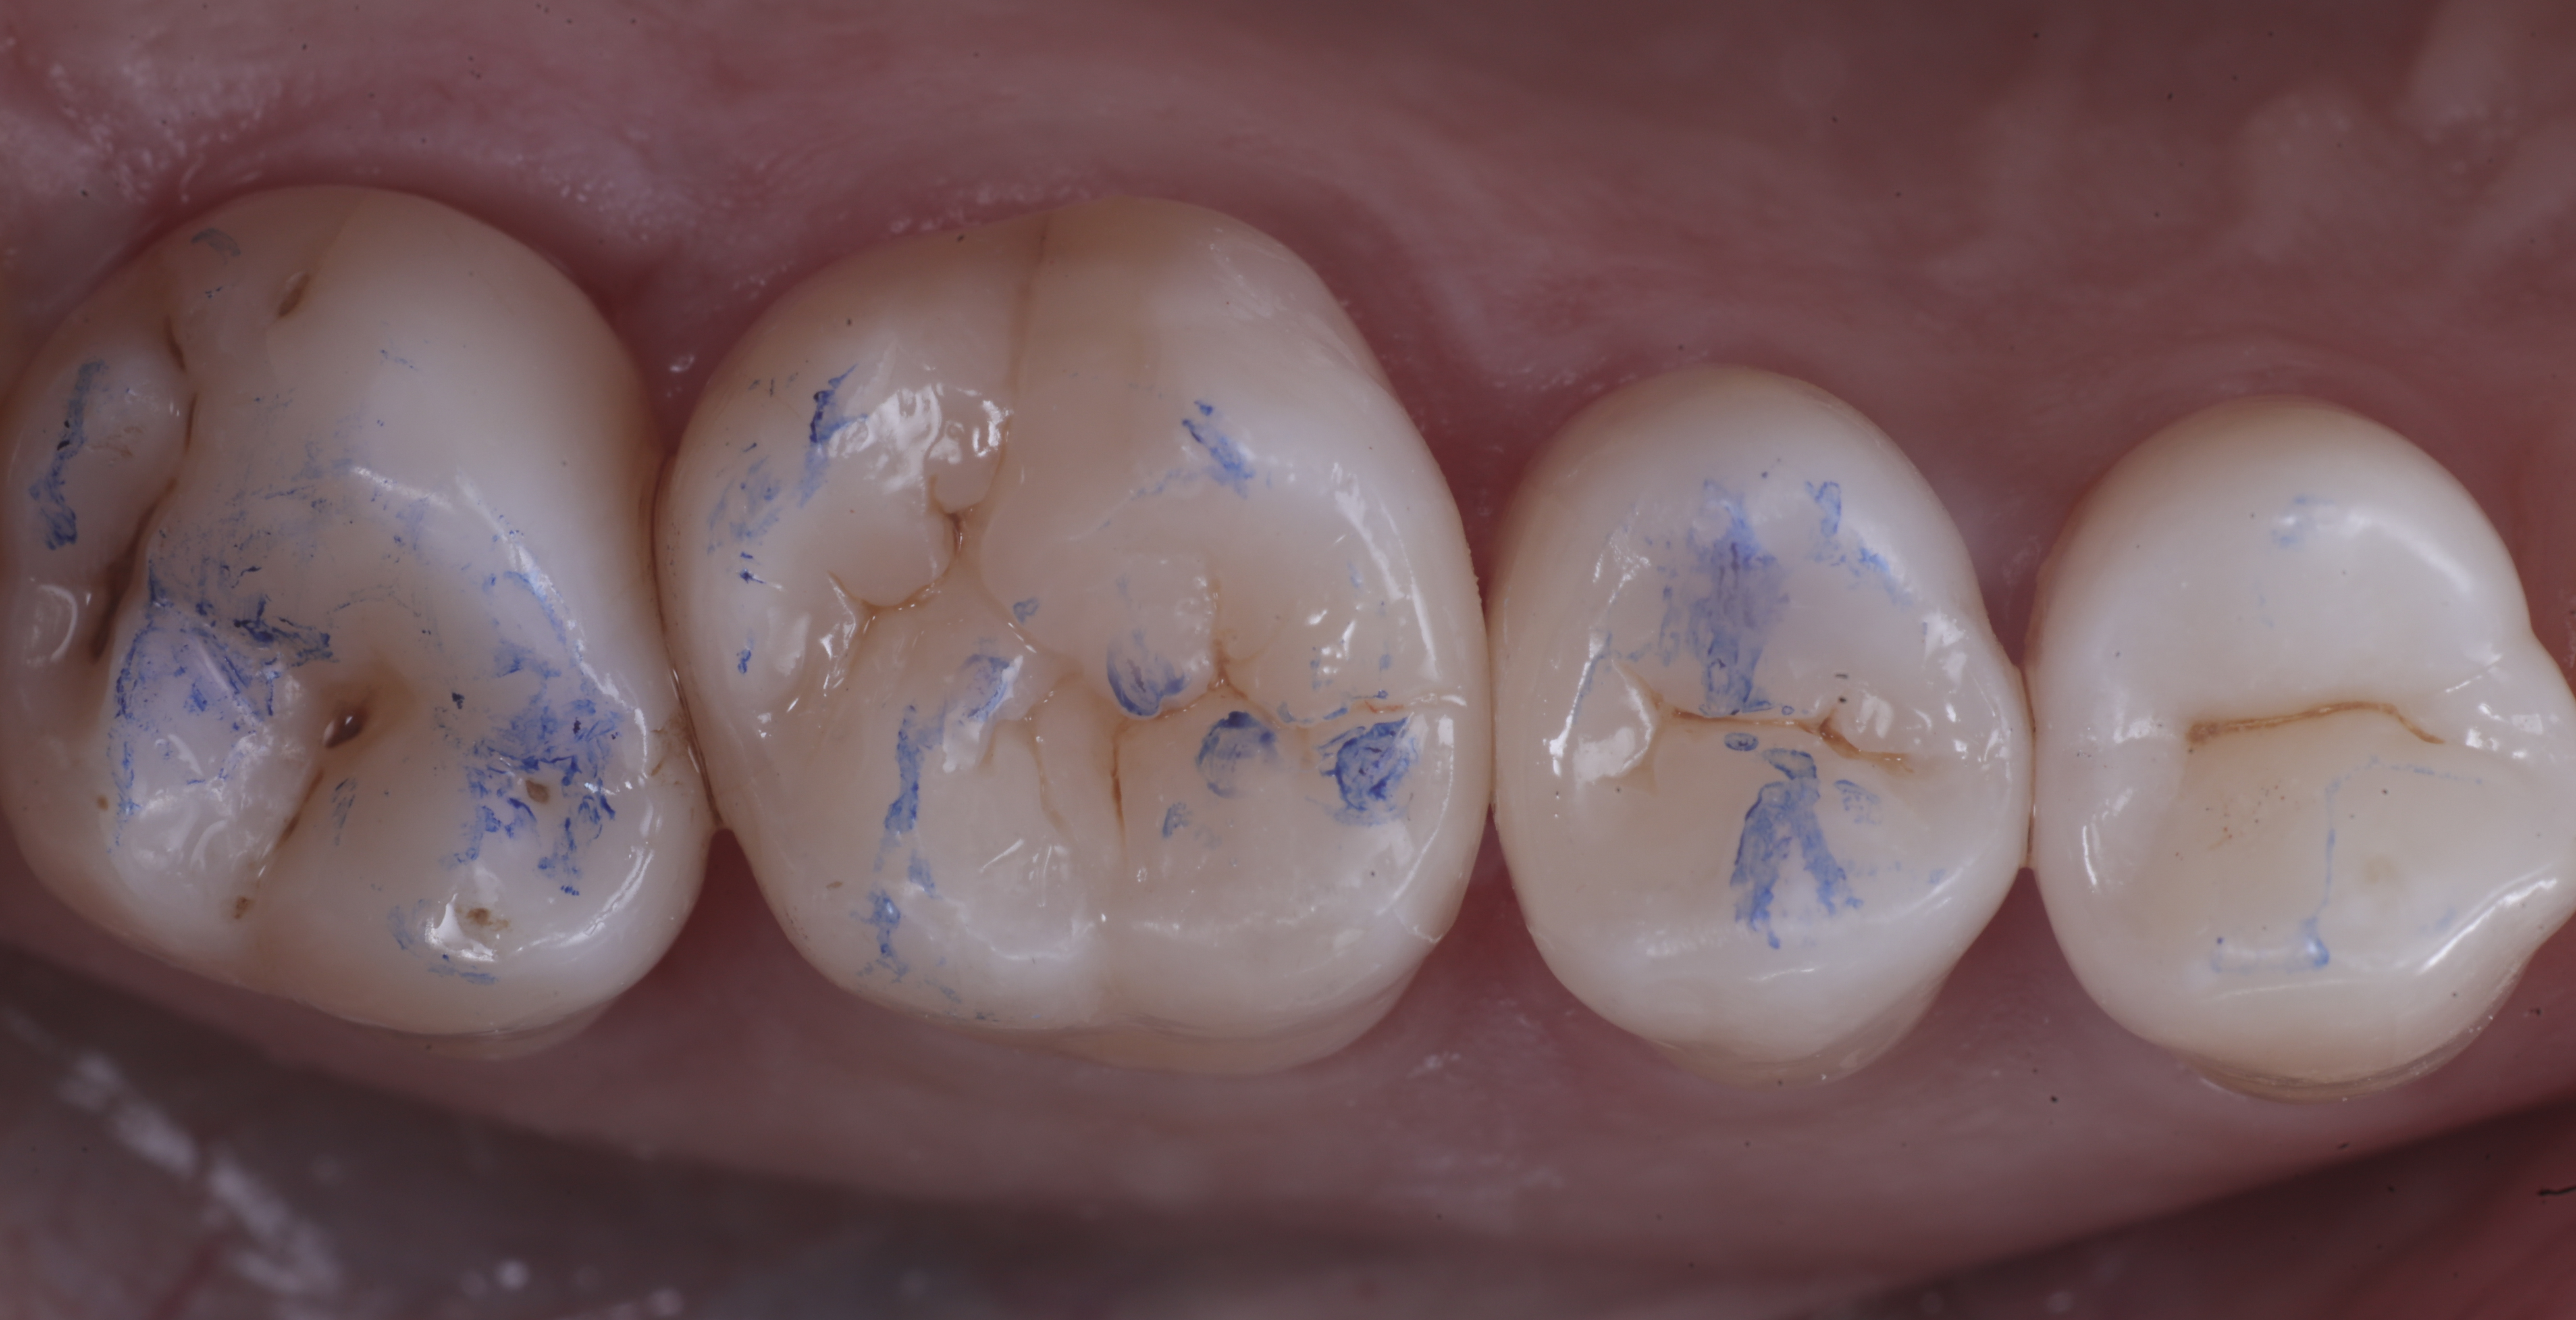

foto 8 Modellazione ed aspetto occlusale

foto 9 Modellazione ed aspetto vestibolare

foto 10 Modellazione ed aspetto palatino

foto 11 Restauri ultimati sotto controllo occlusale